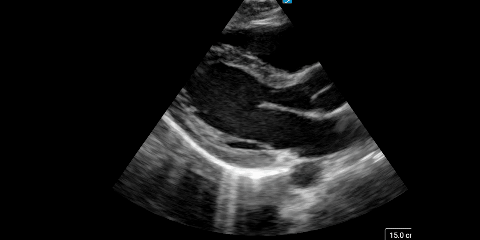

Point of Care Echocardiografie

Snel en doelgericht inzicht in de hartfunctie van je patiënt? Met Point of Care Echocardiografie (POCUS) kun je binnen enkele seconden cruciale diagnostische informatie verzamelen. Deze essentiële techniek helpt zorgprofessionals om levensbedreigende cardiale aandoeningen direct aan het bed te herkennen en de juiste vervolgstappen te bepalen.

Tijdens deze cursus leer je stap voor stap hoe je snel en betrouwbaar cardiale beelden maakt en interpreteert. Je duikt in de anatomie van het hart, de verschillende echovensters en technieken om pericardeffusie, rechterhartbelasting en systolische linkerventrikelfunctie te beoordelen. Met praktische casussen en duidelijke uitleg krijg je de handvatten om deze essentiële vaardigheid direct in te zetten in de klinische praktijk.